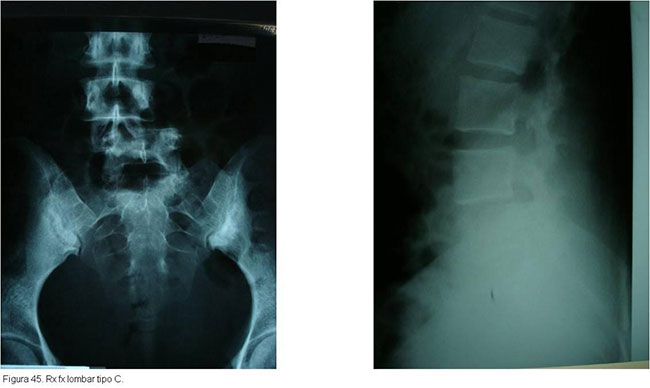

O tratamento seguirá o mesmo raciocínio discutido anteriormente, dependendo de quais estruturas estiverem lesadas. Particularidades da região toraco-lombar e lombar determinarão abordagens especificas caso a caso.(figuras 40, 41, 42 3, 44, 45)